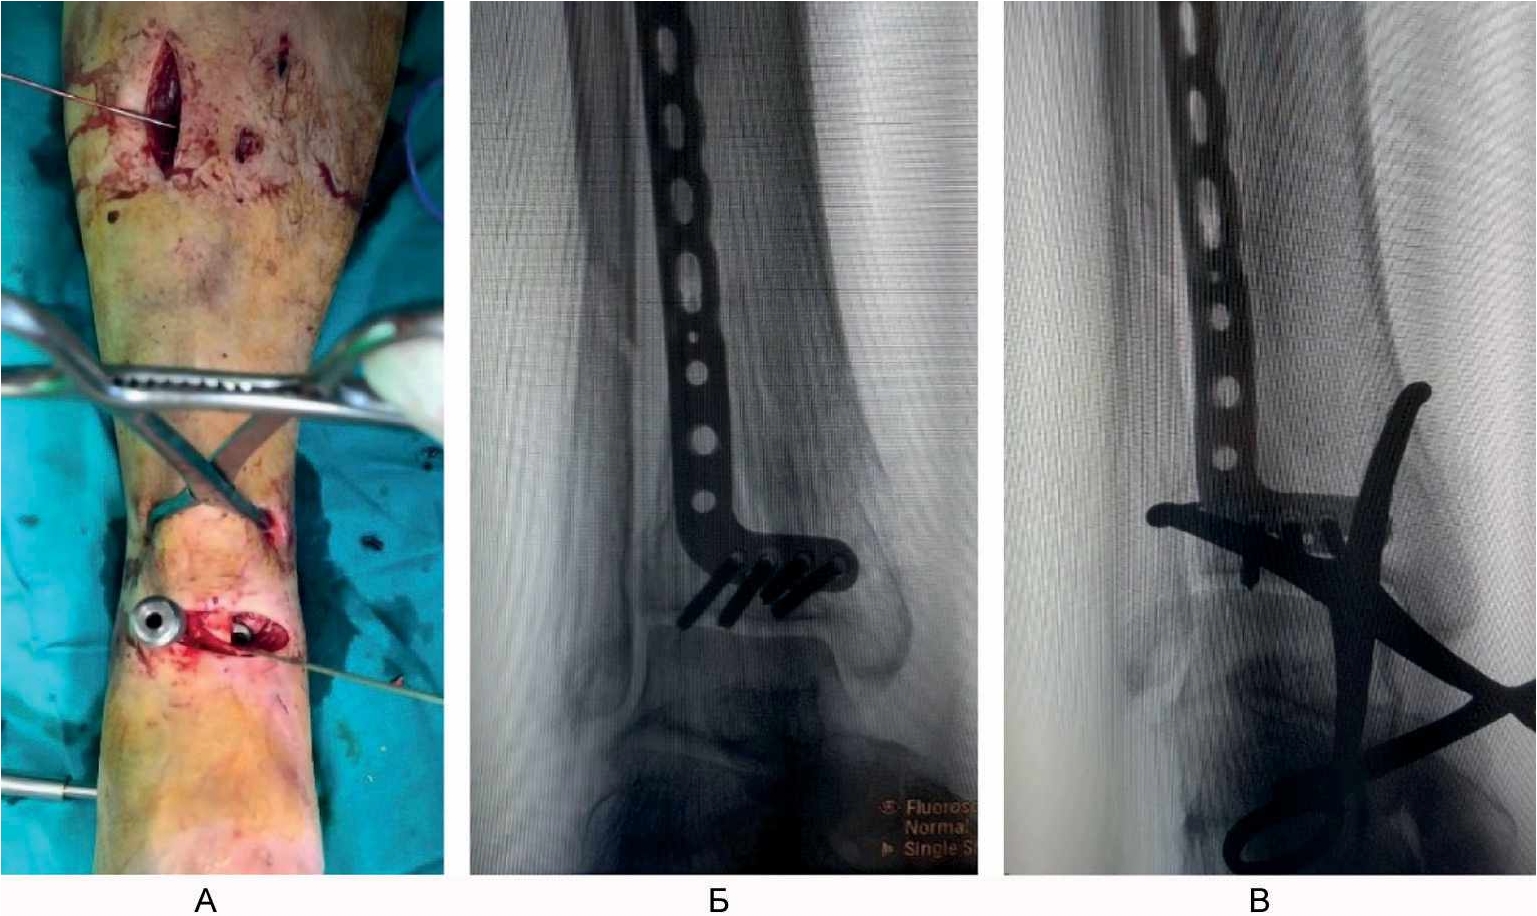

Пациент осмотрен через 3 мес после операции. Он ходит с частичной опорой на оперированную конечность с тростью. Болевой синдром отсутствует. Тыльное сгибание и разгибание голеностопного сустава – в объеме 90–130°, функциональный результат по шкалам AOFAS и Neer [16, 21] составил 71 и 76 баллов соответственно (рис. 7).

Рис. 7. Результат оперативного лечения через 3 мес после вмешательства.

Руководствуясь изложенными соображениями, при предоперационном планировании остеосинтеза у нашего пациента Б., 66 лет, с переломом в области метаэпифиза правой большеберцовой кости и нижней трети диафиза малоберцовой кости мы постарались решить проблему латеральной стабильности с помощью установки опорной переднелатеральной пластины на большеберцовую кость, восстановив ее длину с помощью закрытой тракции в аппарате наружной фиксации (и этот момент мы считаем крайне важным, так как первичное восстановление осевых взаимоотношений и сохранение их в течении дооперационного периода, безусловно, облегчает репозиционные маневры в ходе окончательного остеосинтеза), с последующей установкой пластин через мини-доступы. Фиксация же малоберцовой кости из отдельных доступов в данном случае не потребовалась, так как цель ее остеосинтеза – устранение вальгусной деформации и латеральная стабильность – была решена остеосинтезом самой большеберцовой кости. Правомерность выбранной нами тактики в случае у нашего пациента была доказана клиническим и рентгенологическим сращением перелома большеберцовой кости, отсутствием при этом вторичного смещения отломков и хорошим функциональным результатом.

Контрольные рентгенограммы в прямой (А) и боковой (Б) проекции – определяется сращение перелома; В–Д – функциональный результат лечения.